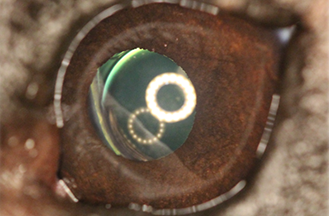

- Postoperative Bilateral Phacoemulsification Outcomes in Dogs Receiving Subconjunctival Triamcinolone with or without Topical Anti-inflammatory Therapy (“dropless” cataract surgery)

- Post‐operative Outcomes of Phacoemulsification in Juvenile Dogs